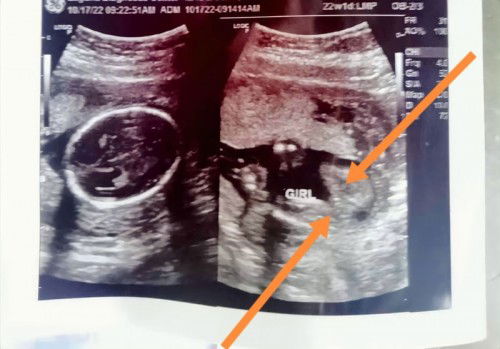

Baby gender

3yrs old boy And Pregnant 5months Mga mi, ask ko lang po ano sa tingin nyo? Girl po ba talaga kapag ganyan? Sabi po kasi 80% girl. I have a 3yrs old na po and boy sya. Sobrang nakakakilig lang kung sure na may baby girl na kami hehe. :) Planning to have another ultrasound kapag 8 months na tummy ko for checking kung sure na hehehe.